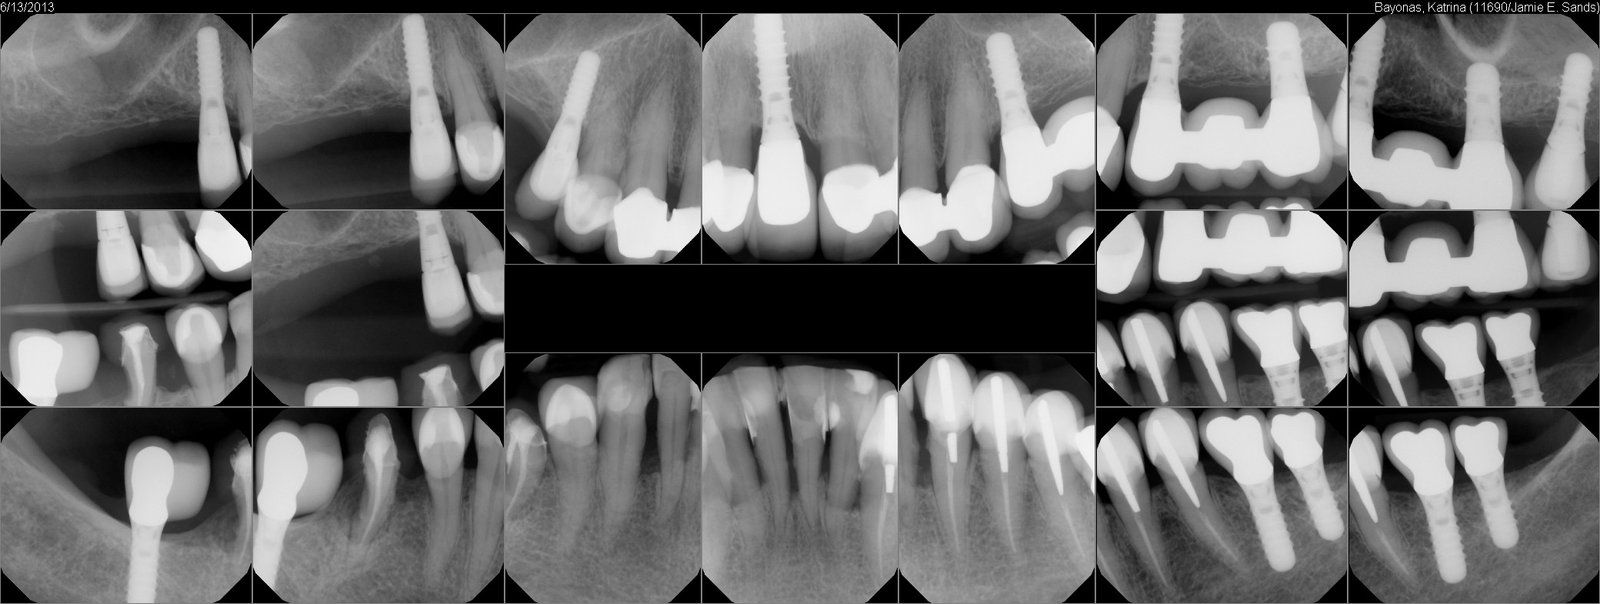

Buenos días: Tengo una paciente que necesito rehabilitar pero desconoce marca del implante y medidas.A la paciente le suena que pueden ser marca Straumann Podéis ayudarme a saber marca y [...]

La paciente se realizó el implante en Francia hace 20 años y quiere cambiar La Corona. ¿Sabéis que marca es y diámetro? Y ¿ donde puedo conseguir transfer?. Gracias